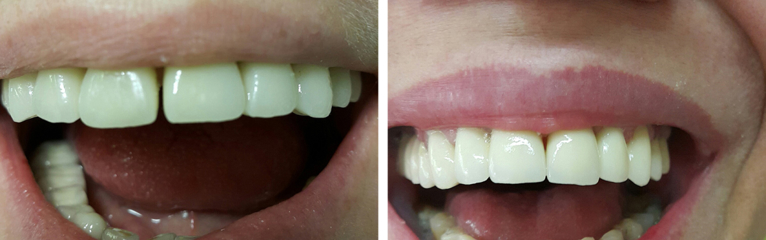

Protetika: prije i poslije. Foto: Dental Centar Jelić